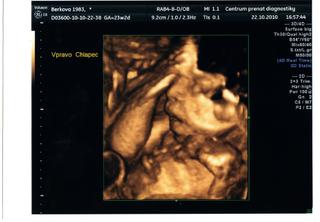

tak včerejší 3D UTZ nic moc 😅 ale to se dalo čekat že? Ale tentokrát mi to bylo tak nějak víc jedno než u NIny, dneska pro mě byly důležitější jiný věci. Mimuška jsou zdravá, mají obě půl kila. Eli je hlavičkou dolů, Mari je příčně přes ni, takže máme fotku jen Mariho, páč Eli už nešla vůbec vidět. Ale pro mě je zážitek jenom to, že je vidím 😵 😵 😵